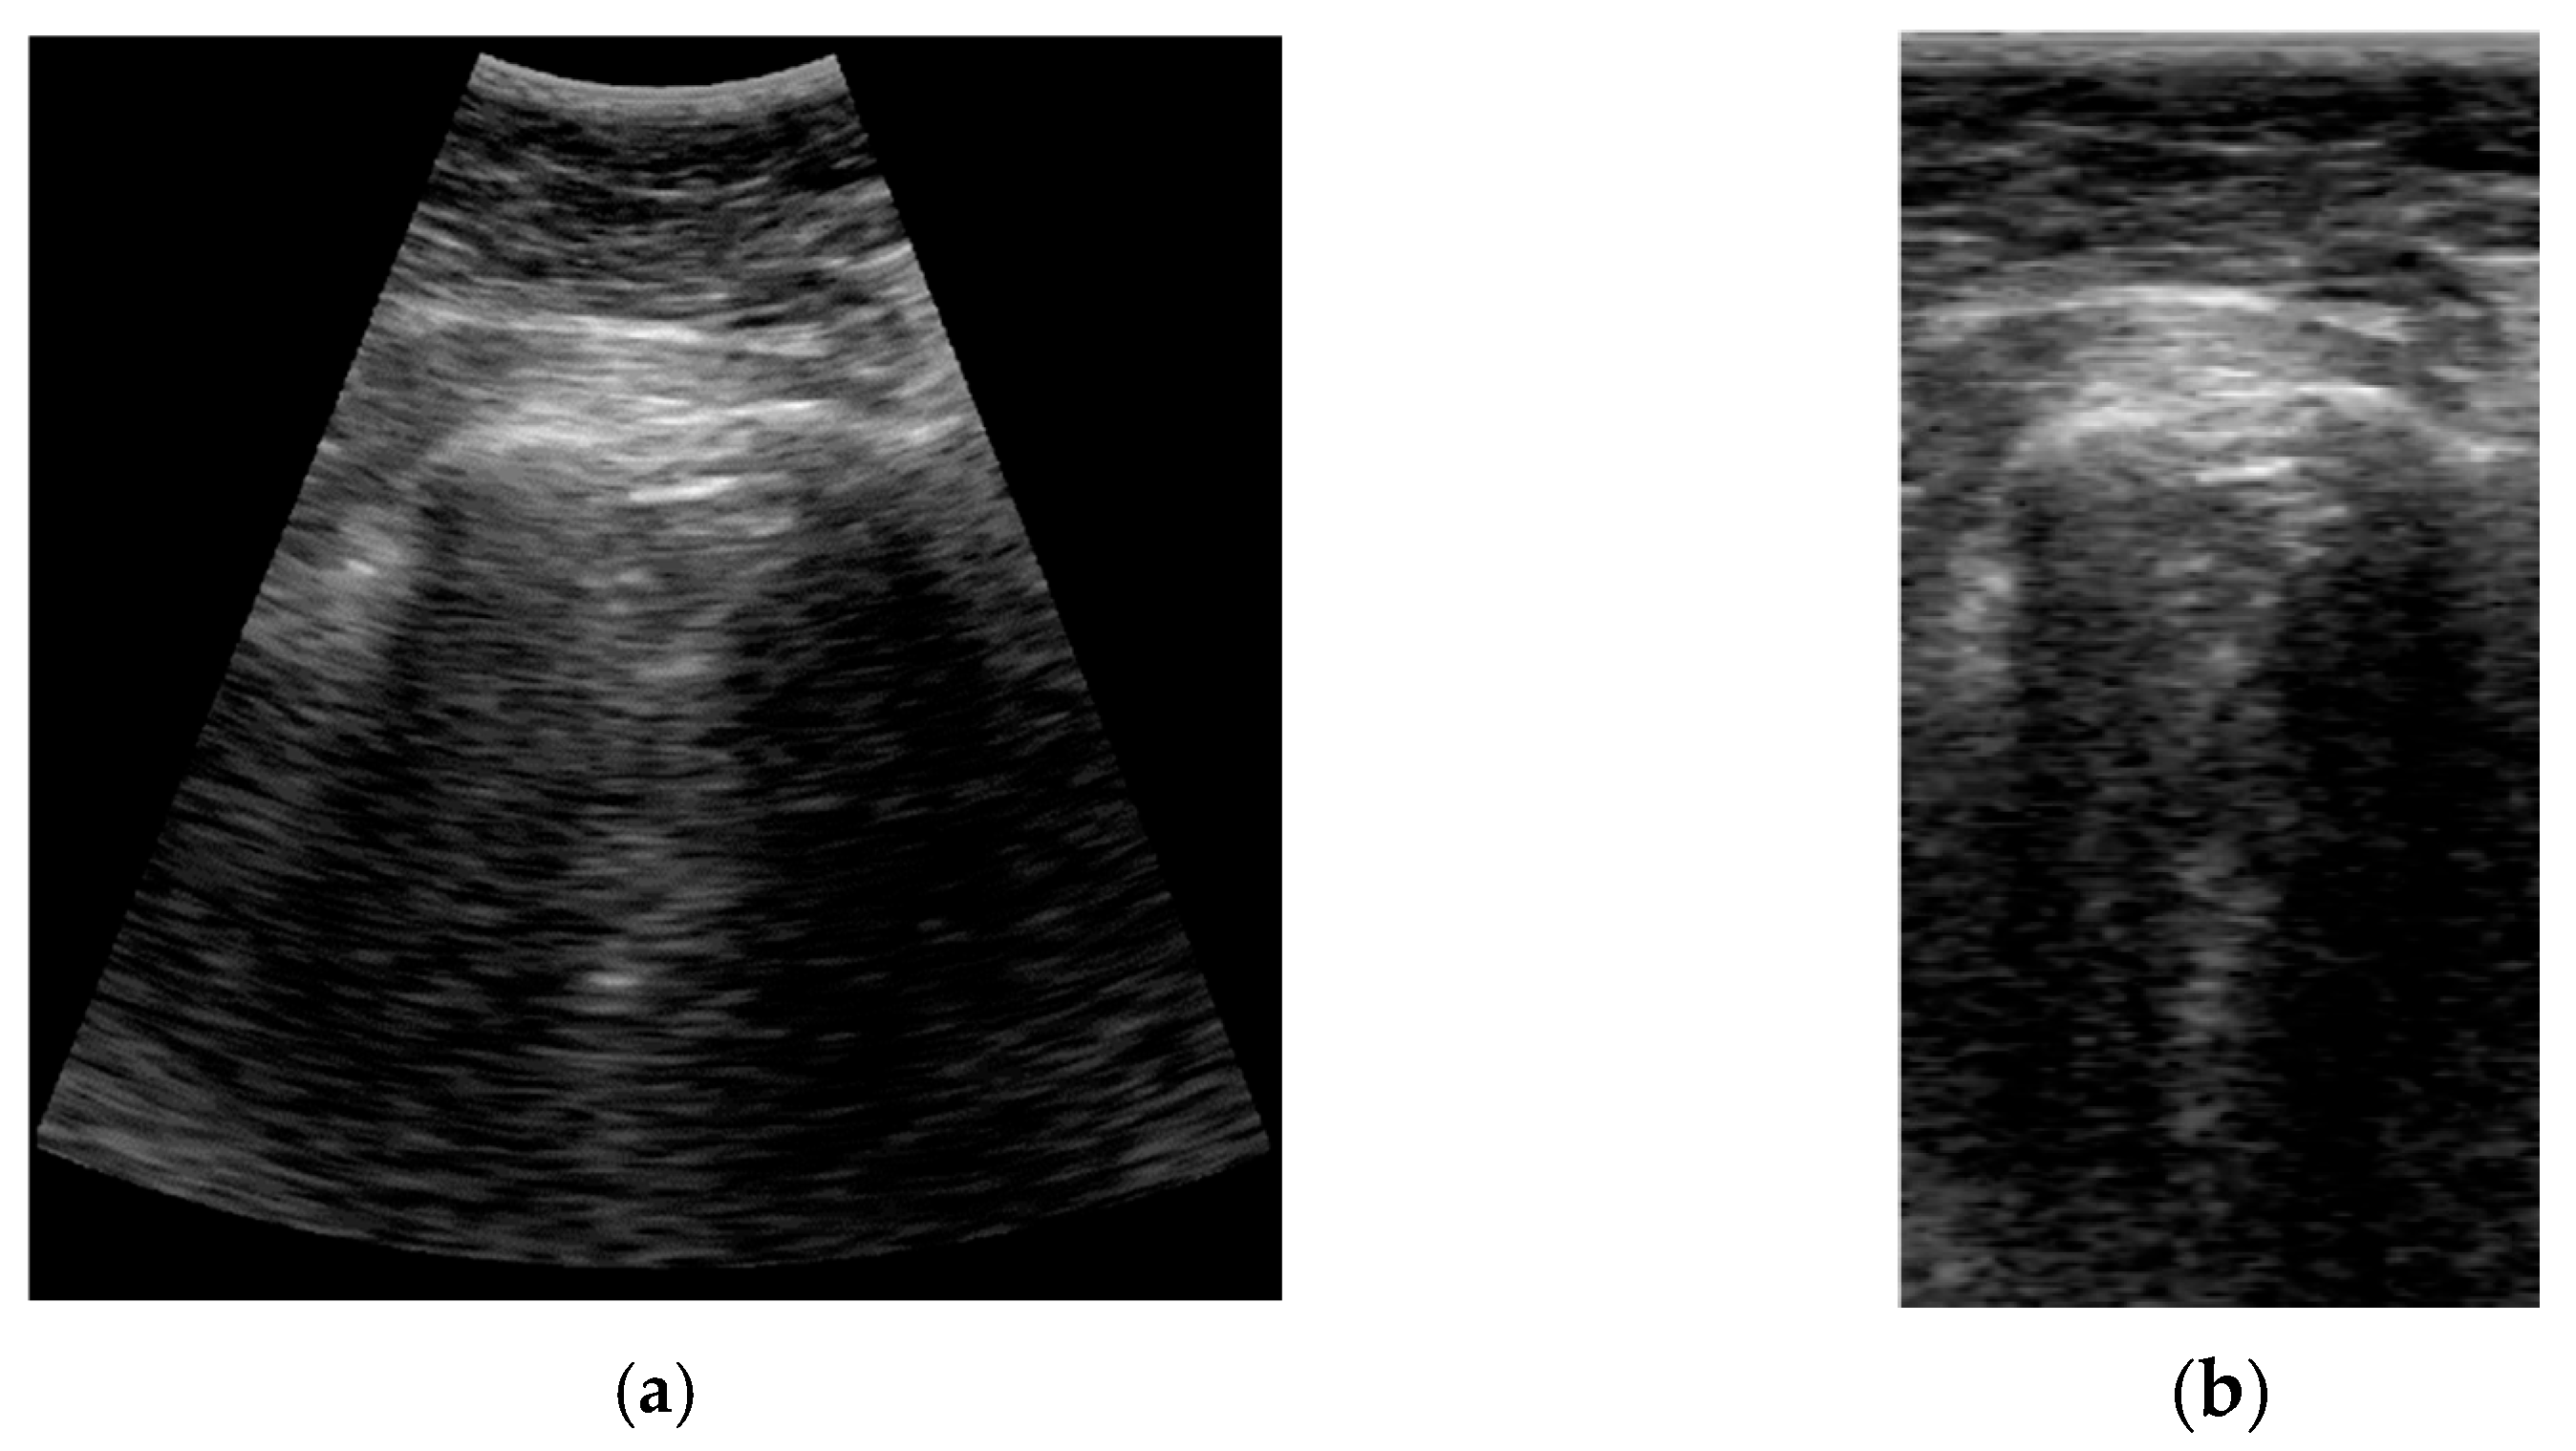

The format of the input data has a great impact on the deep learning model definition and performance. A typical ultrasound image with a curved array (like that used in this study) is a circle sector, defined by an aperture angle α, an initial range r1, and a final range r2, which is usually framed into a rectangular image with size W × H pixels (Figure 2 Left). But, in fact, a sector ultrasound image is originally formed by N scan lines usually equally distributed inside the sector area. These lines, containing M samples each, are the output of the beamforming algorithm, and could be interpreted themselves as a rectangular image (Figure 2 Right).

Figure 2.

Possible representations of an ultrasound sector image: (left) conventional pixel-based image given by ultrasound scanners; (right) B-Scan rectangular image formed by ultrasound samples only, without geometrical information of the probe.

The algorithm to obtain the sector image from the B-Scan data is usually called scan-converter, and it is typically implemented by bi-linear interpolation of the acquired samples over the pixel grid. This process is carried out by the scanner, which gives the user the sector image in W × H format. Therefore, a question arises about which image format is more appropriate for implementing the deep learning algorithm aimed at in this work.

Sector image has the advantage of being more easily accessible, because it is the typical output format for most ultrasound equipment. Therefore, it maintains the aspect ratio of the structures to be imaged, which eases interpretation by medical professionals. However, accommodating a sector image inside a rectangular grid generates black margins around it, which, besides adding pixels with no information, could potentially introduce a bias in the automated image analysis. Furthermore, the shape and extension of these zones depends on the scanner model and the configuration, hindering the translation of the resultant model between different scanners.

On the other hand, rectangular B-scan images have the advantage of providing only useful information (no black margins), while its rectangular format is highly suitable as input for segmentation models. Another important advantage is that each vertical line represents a physical propagation direction of the beam inside the tissue, which is particularly relevant for artifacts like B-Lines, that appear precisely on those directions. Therefore, a B-Line will be always seen in the B-Scan as a vertical artifact, independent of its position on the pleura and of the scanner configuration. Furthermore, scanner configuration parameters like the aperture angle α or the initial and final range r1 and r2 only affect the size M × N of the image, which simplifies adapting images acquired with different configurations to the same network, only by vertical and horizontal scaling.

On the other hand, these images are not suitable for visual interpretation, as they present a distorted view of the tissue anatomy. Because not all ultrasound equipment provides direct access to B-Scan data, a Sector-Image-to-B-Scan conversion algorithm would be needed. With a similar approach than scan-converter algorithms from B-Scan to sector image, it could be based on a simple bilinear interpolation algorithm after defining a set of beam lines that cover the useful area of the sector image (green lines in Figure 2 Left). In this work, we had access to the B-Scan raw data generated by our system, so no Sector-Image-to-B-Scan process was needed.

The size of the vertical direction is related to the frequency content of the signal and the sampling rate. For an ideal 100% bandwidth array, the maximum frequency content of the signal envelope is equal to half the array center frequency. To reconstruct the envelope without aliasing, the pixel density in the vertical direction should be, at least, able to sample the signal at double of that frequency (Nyquist criteria). For the array used in this work with 3.5 MHz center frequency and 70% bandwidth, the number of pixels required for sampling up to 70 mm and 90 mm is 210 and 294, respectively. Based on these numbers, a height of 256 was selected for the network, which imposes a trade-off between training and inference cost and image quality. In cases when larger images are used, they should be scaled down using compression algorithms that preserve the artifacts’ information. For example, in the scanner used in this work, a data reduction algorithm without peak information losses is available [26] and was used to accommodate the B-Scan height to the network size. In Figure 3, a comparison example between sectorial and B-scan images is shown.

Figure 3.

Comparison between sectorial image (a) and B-Scan (b).